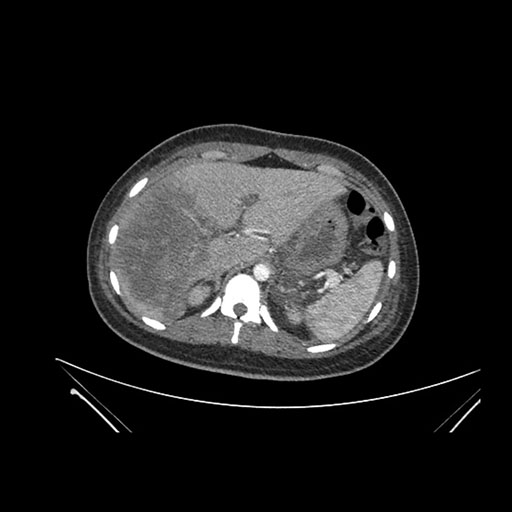

Imaging Analysis

Look through the patient's CT scan to identify any areas of concern for the necessary procedure.

Axial Arterial

Based on initial findings, which issue(s) would you be most concerned about?